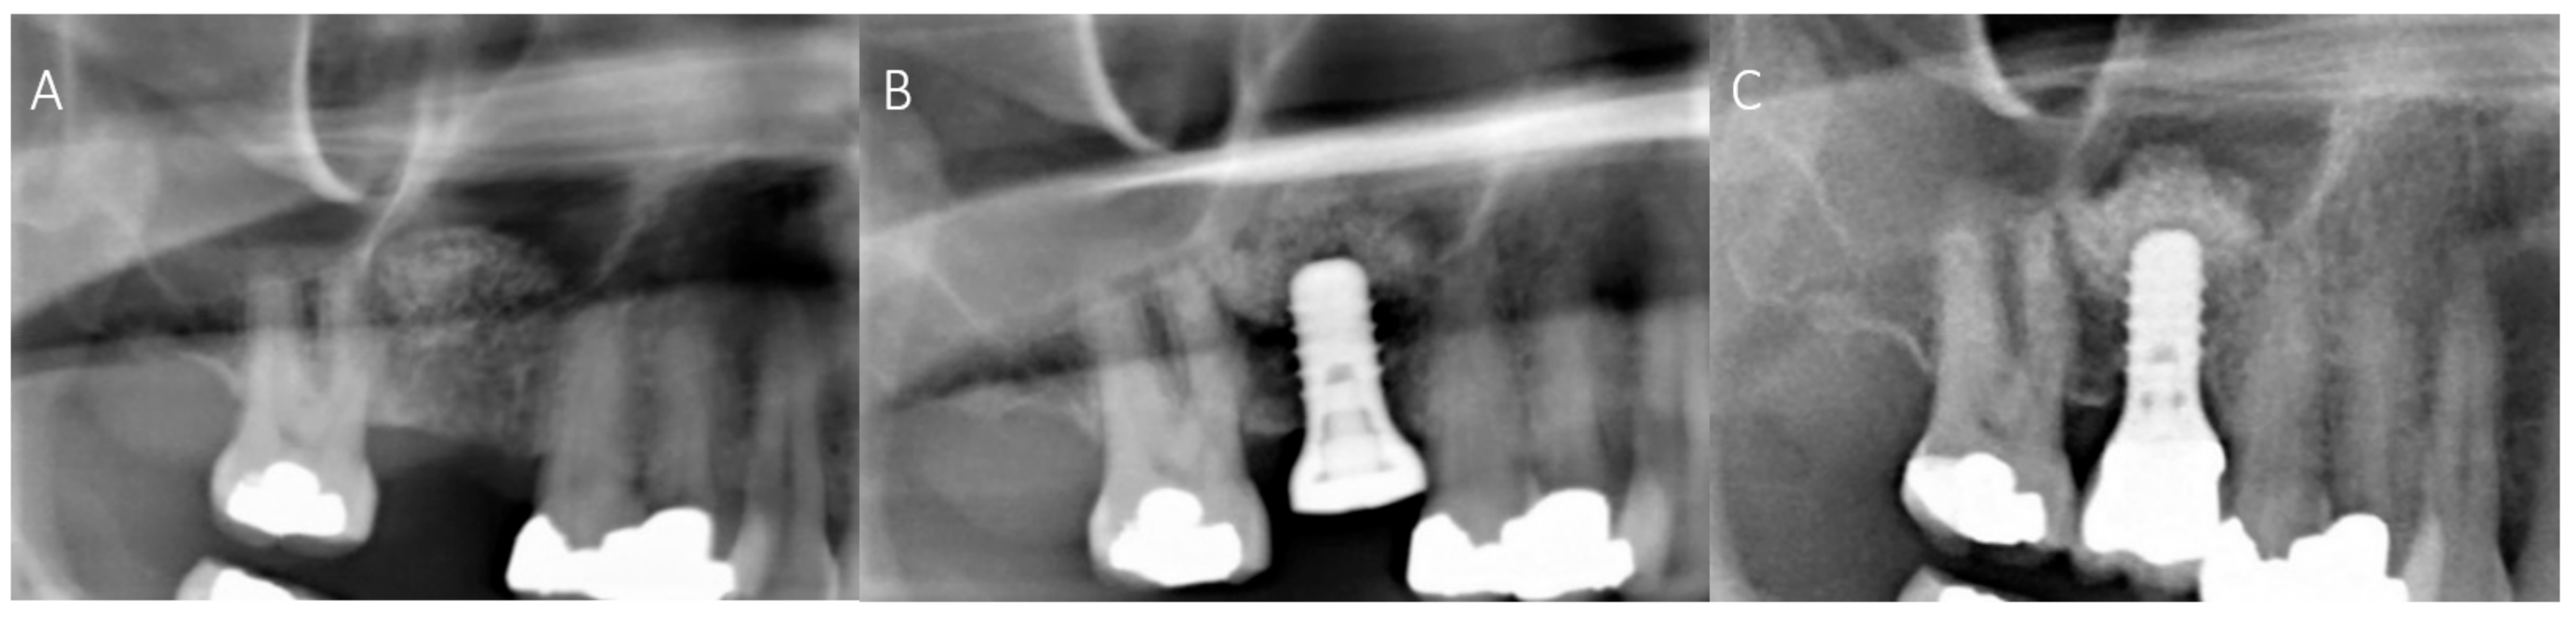

2.4. Radiological Evaluation